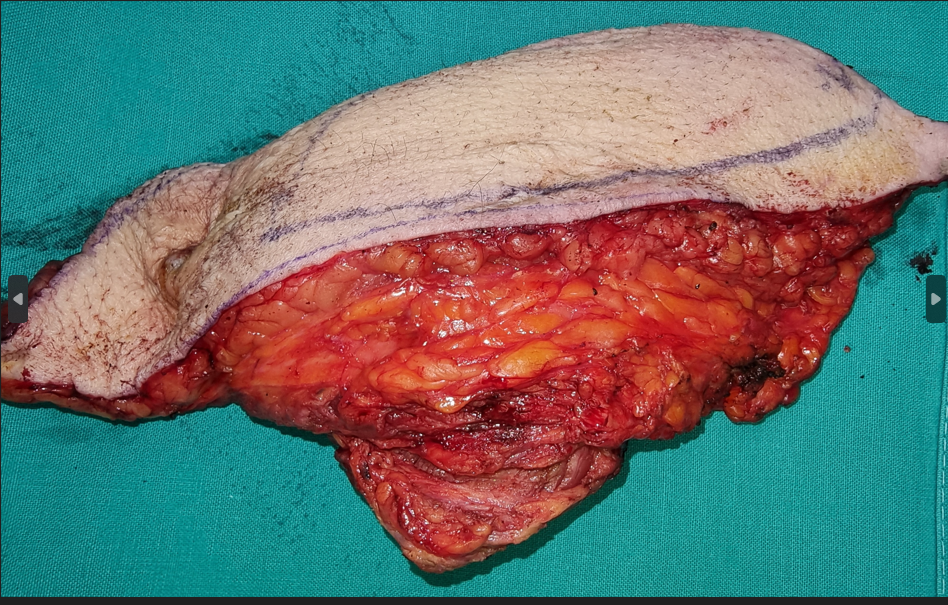

Καρκινωματώδης λεμφαγγειΐτιδα. Εύρημα νεκροτομής (Ευγενική παραχώρηση Dr. V. Penopoulos)